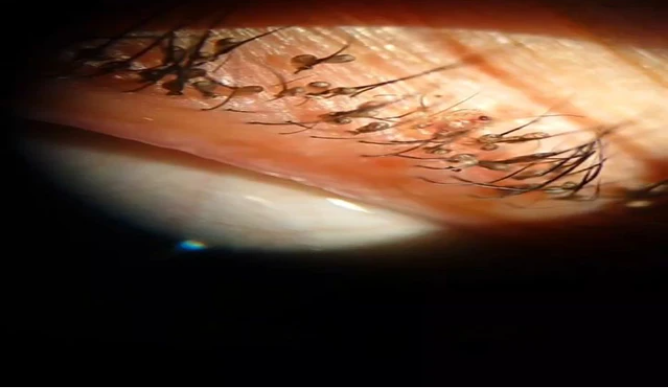

Các bác sĩ đã tiến hành soi mắt bệnh nhân dưới kính hiển vi và bất ngờ phát hiện dưới lớp vảy mí mắt có rất nhiều rận mu bám chi chít. Trên lông mi, rận đã đẻ trứng thành chuỗi.

| Dưới lớp vảy mí mắt của bệnh nhân xuất hiện nhiều rận mu bám chi chít. Ảnh BVCC |